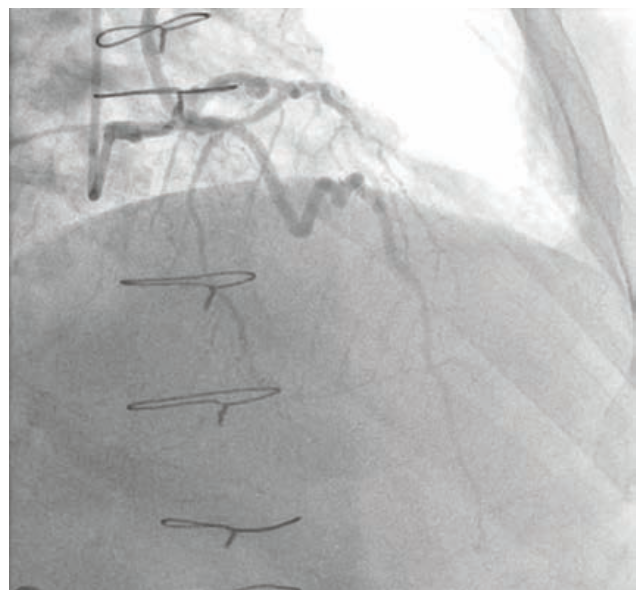

Dual access was achieved with a 7 French Amplatz Left (AL)-1 guide catheter and a 7 French Extra Backup (EBU) 3.75 guide catheter. Based on dual-injection angiography, the proximal cap was ambiguous due to a tortuous right ventricular (RV) marginal branch and the occlusion was long (>20 mm) (Figure 1). Therefore, we decided to attempt retrograde techniques first. After administering heparin to a goal activated clotting time (ACT) of >350, a workhorse wire was advanced through a low-profile microcatheter into the first septal perforator. The wire was exchanged for a specialty wire that was used to cross septal collaterals. We had difficulty advancing the microcatheter into the septal perforator, as it was jailed with a previously placed stent (Figure 2). Here, we used a 1.5 mm x 20 mm TAKERU balloon to dilate the stent struts. We were able to advance the microcatheter into the septal perforator and into the distal vessel (Figure 3). The connection was made with a reverse controlled antegrade and retrograde tracking (R-CART) technique (Figure 4). Overlapping drug-eluting stents were placed and aggressively post dilated. Final angiography demonstrated no residual stenosis, dissection, or perforation (Figure 5). The patient was placed on dual antiplatelet therapy for six months.